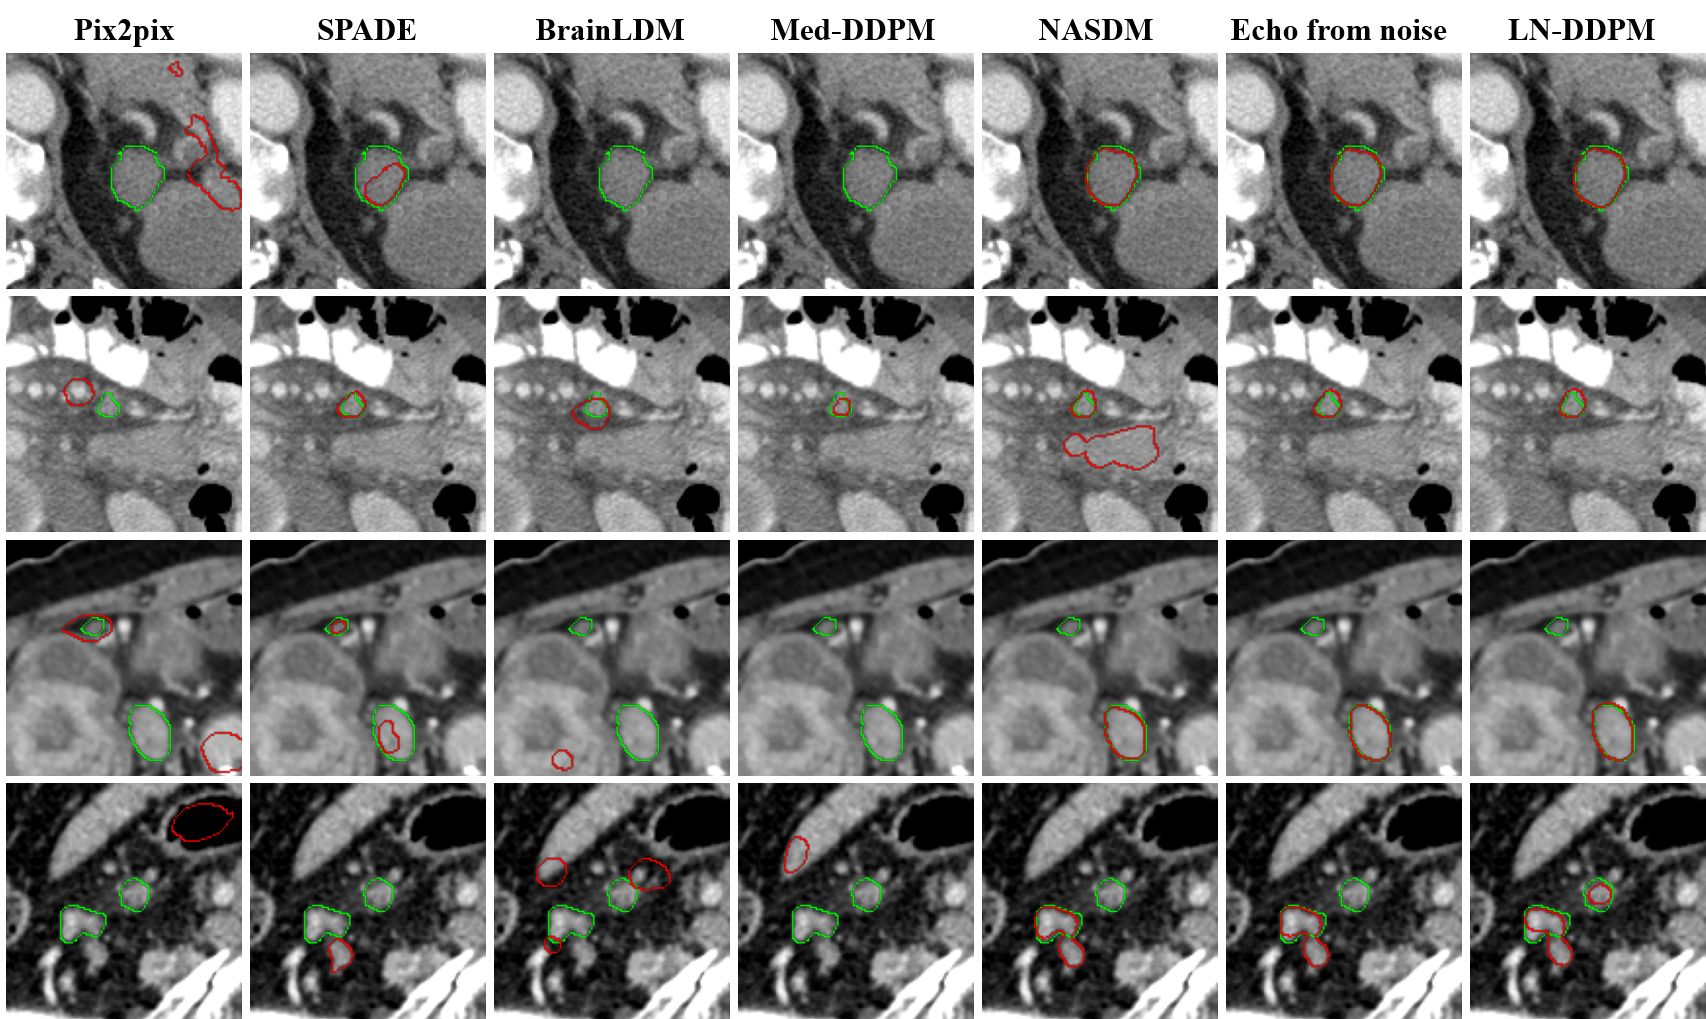

When training the nnU-Net model exclusively with synthetic data, our proposed LN-DDPM gains better DSC, Recall, ASSD, and NodeRecall of 0.5376, 0.5830, 8.8986 mm and 0.7486, respectively, while maintaining a similar IOU of 0.3958 compared to training with real abdominal lymph node images. However, the Precision is inferior to training with real abdominal lymph node images primarily because those synthetic images are lymph node region images and lack richer information about abdominal environment. The visualized segmentation results of different generative approaches when training with only synthetic data are depicted in Fig. 5. LN-DDPM is capable of discovering the majority of abdominal lymph nodes with fewer false positives and achieving better segmentation accuracy. Notably, in the last row, only LN-DDPM segments the upper right lymph node. However, LN-DDPM fails to detect the small upper left lymph node in the third row.